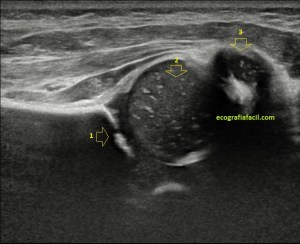

236. Quiste parameniscal.

El fin de semana pasado os pregunté en instagram a cerca de dos semiologías patológicas que me pareció que os gustaría ver, una de ellas era el quiste parameniscal, la otra la lipomatosis, ganó muy ajustadamente la lipomatosis, pero el caso que os iba a presentar al respecto tiene lagunas que por el momento hace que no pueda desarrollarlo convenientemente y por tanto el caso que nos ocupará hoy es la otra opción, no por ello menos bonita, es el quiste parameniscal.

El paciente es un hombre de 44 años con dolor de rodilla en la cara externa, ha sufrido varias cirugías por meniscopatías en el lado externo de la rodilla mientras realizaba una práctica deportiva, pero de este evento quirúrgico hace ya años. Acude al médico por dolor en la región previamente señalada, su médico le remite para valoración.

Lo primero de todo es saber cómo debemos ver un menisco en la ecografía, para ello debemos buscar la cara lateral, interna o externa que deseemos estudiar, con sonda lineal de alta frecuencia, corte longitudinal o eje largo respecto de la rodilla a estudio, es decir, como si hiciésemos un corte coronal de la misma.

Que debemos encontrar, bien, algo parecido a esto:

Esta es la normalidad, es una imagen preciosa cedida por Javier Álvarez @fisioequilibra, TSID, Fisioterapeuta, Profesor de la Universidad Francisco de Vitoria de Madrid, colaborador del Blog y amigo de los que se cuentan con los dedos de la mano…

Es lo primero que debes buscar, es lo más importante. En la imagen  1 puedes ver un menisco normal y sano, señalado por la flecha hueca amarilla. Semiológicamente es una estructura cónica hiperecogénica, homogénea en la cara externa de la rodilla entre la tibia y el cóndilo femoral, profundo al ligamento colateral, es la parte visible del menisco por ecografía y es tu objetivo en cada exploración de esta zona.

En el caso de hoy, el paciente presentaba una imagen de la zona descrita en la imagen 1 y que ves la imagen siguiente que difiere significativamente de la normalidad.

2

En esta imagen vemos la misma región que viste en la imagen 1, donde claramente ves alterada la semiología de la ecoarquitectura de menisco, heterogéneo, hundido, y en la superficie del mismo, imágenes hipecogénicas muy finas que pueden indicar afectación del mismo. Un poco más superficial e indicado con la flecha roja observas una estructura anecoica, correspondiente a líquido que luego verás en detalle en fotos posteriores.

La afectación del menisco es variable, por supuesto, verás muchos que difieran de la normalidad. En la imagen 2 has visto un menisco afectado, en la imagen 3 vas a ver otro, mira:

3

En la imagen 3 puedes ver un menisco que en su parte central tiene una línea hipoecogénica, bastante sutil, fíjate bien, irregular que lo divide en 2 partes. Pero ¿qué pasa cuando un menisco está dañado? Cuando un menisco por sobreuso, sobrepeso o la razón que sea pueden mostrar cambios en la ecoestructura, ya sea por que se han fisurado, como el de la imagen 2, incluso pueden llegar a romperse. Es fisura o rotura puede ser la vía de escape del líquido intraarticular de la rodilla hacia la parte extraarticular y si eso se produce, podemos encontrarnos con esto:

4

El líquido ya se ha salido y ha formado una bolsa situada superficial al menisco, profundo al ligamento colateral y que está señalado con flecha amarilla. Marcadamente anecoico puedes verlo en tamaños variables en función el alcance del líquido que haya salido y en función de las variantes propias de cada paciente.

La presentación de éste era así:

5

Semiológicamente ves una ecoestructura anecoica con septos hiperecogénicos paralelos en alguna porción del quiste que no muestra vascularización. Este estaba en torno a los 2,5 cms, en el momento de la exploración.